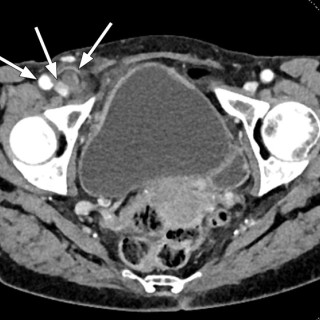

CT-bildet viser et 37 mm stort aneurisme i portvenen, inklusive stammen til vena mesenterica superior og grener til denne. Pasienten var en kvinne i 40-årene med tidligere anoreksi. Hun hadde i fire uker vært plaget av diffuse magesmerter og tidlig metthetsfølelse. Klinisk undersøkelse og orienterende blodprøver hos fastlege, herunder leverprøver, viste normale funn, og hun ble henvist til CT. Portveneaneurisme er en sjelden tilstand (1). Om lag 200 tilfeller er beskrevet i litteraturen, og kunnskapsgrunnlaget bygger på kasuistikker og pasientserier. Det defineres som en fokal dilatasjon i...